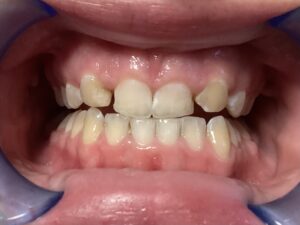

This patient arrived at my practice last week with 2 congenitally missing laterals incisors. Her orthodontist moved the canines into the position of the lateral incisors to fill the gaps but canines don’t look like incisors. They are pointy and “fat” so I told them upfront that although perfect aesthetics will not be achieved we can greatly improve the look and also remove the decay. The procedure required a single 2hr appointment and a very pleasing result was achieved with a very happy teenager leaving the practice that day. Further improvements can be done at a next visit by removing the white spots on the first premolars.